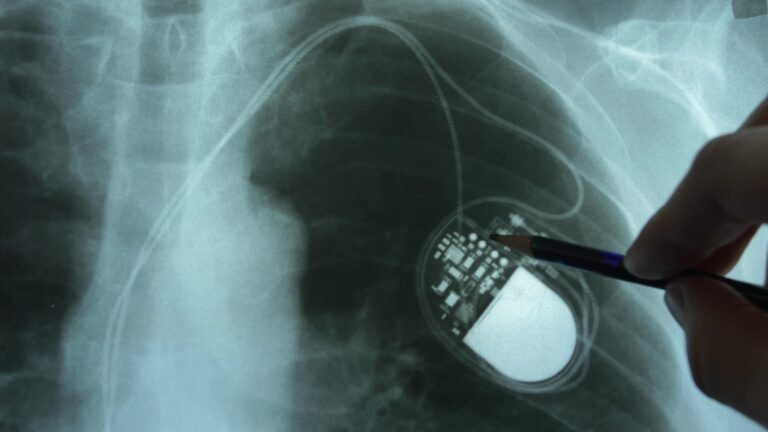

Le cardiologue spécialisé réalise une incision de 5 à 10 cm sous la clavicule, créant une petite loge entre la peau et le muscle pectoral. Les sondes sont introduites par la veine sous-clavière jusqu’au cœur, leur position étant vérifiée par radiographie.

Une fois les sondes positionnées dans le ventricule droit, le médecin les connecte au boîtier du stimulateur avant de refermer la plaie. Un pansement compressif protège la zone opérée pendant 24 heures.

Un pacemaker est constitué de deux parties : la batterie et les sondes. La batterie ou pile, en lithium, est enfermée dans un boîtier en titane placé sous la peau (hors du cœur). La durée de vie moyenne de la batterie est de 6 à 8 ans. Les sondes électriques, quant à elles, sont placées dans le cœur via une veine et reliées au boîtier. Selon le type de bradycardie, on en placera une ou deux. Les sondes détectent le rythme cardiaque du patient et transmettent les informations au générateur du pacemaker. Si la fréquence des pulsations cardiaques est trop lente, le pacemaker délivre alors des micro-impulsions électriques pour stimuler le muscle cardiaque, qui se contracte.